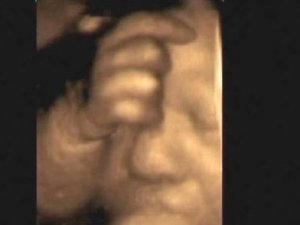

7 aylık bebeğin mucizevi görüntüleri

Anne karnındaki davranış biçimlerinin doğumdan sonra da devam ettiğini ifade eden Medicana Hastanesi Kadın Hastalıkları ve Doğum Uzmanı Prof. Dr. Metin Çapar, bazı ailelerin çekilen ultrasonografik görüntüleri hatıra olarak sakladıklarını söyledi. Bebeklerin anne karnında değişik hareketler yaptığını vurgulayan Prof. Dr. Çapar, geçen 7 Mayıs günü, 7 aylık bir bebeğin elini emerken görüntüsünün net bir şekilde çektiğini de vurguladı.